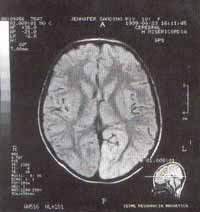

Al ingreso, signos de desnutrición crónica dados por hipotrofia muscular generalizada, consciente, alerta, con nistagmus horizontal de predomino izquierdo, hemianopsia homónima izquierda, marcha insegura, pulsos periféricos y carotídeos normales, no hay otros hallazgos anormales al examen físico. Se tomó TAC cerebral, el cual es compatible con evento isquémico agudo en territorio de la arteria cerebral posterior derecha. La RM cerebral mostró hipointensidad córtico subcortical temporooccipital basal parasagital derecha en T1, hiperintensa en T2 y protones, el resto de estructuras cerebrales y vasculares se aprecian normales; compatible con evento vascular isquémico subagudo en territorio de arteria cerebral posterior. (fig. 1)